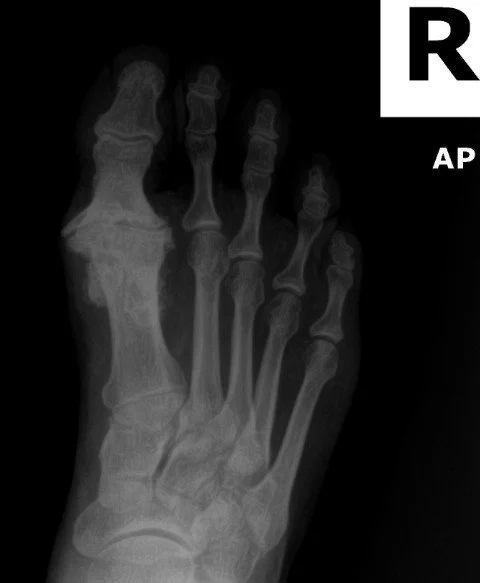

severe hallux rigidus, big toe arthritis, of the foot. Xray of the foot showing arthritis

Hallux rigidus is the most common arthritic condition in the foot, affecting about 2.5% of people over age 50¹. The term literally means “stiff toe” in Latin, and refers to degenerative arthritis of the big toe joint. Over time, the smooth cartilage lining the joint wears away, leading to stiffness, pain, and bony overgrowths (spurs). Unlike a bunion, which pushes the toe sideways, hallux rigidus causes the joint to lock up and lose motion.

• X-rays: Weightbearing AP, lateral, oblique to evaluate joint space, spurs, sesamoid changes

• Grade 1: Mild stiffness, minimal radiographic changes

• Grade 2: Moderate stiffness, dorsal spurring, joint space narrowing

• Grade 3: Severe stiffness, large spurs, marked joint narrowing

• Grade 4: End-stage arthritis, near-total motion loss